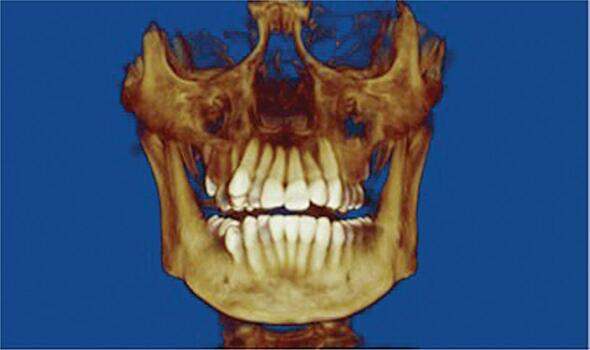

Ученые из первого МГМУ им. Сеченова разработали новый подход к диагностике трещины корня зуба с помощью конусно-лучевой компьютерной томографии (КЛКТ). Новый подход позволяет обнаруживать костный дефект в области трещины, даже если саму трещину обнаружить не удается. Подробности исследования опубликованы в журнале International Endodontic Journal. В корне зуба может образоваться вертикальная трещина. Осложнение может приводить к воспалительному процессу и к разрушению костной ткани. Сложность диагностики заключается в том, что стандартная рентгенограмма не позволяет визуализировать линию трещины. Конусно-лучевая компьютерная томография могла бы решить проблему, но в клинической практике метод дает низкое пространственное разрешение. Тем не менее, конусно-лучевая компьютерная томография позволяет получать 3D-изображение костной ткани в области трещины. Ученые сравнили точность двух методов диагностики при помощи КЛКТ: визуализируя линию трещины или анализируя характеристики костного дефекта. Было впервые показано, что второй метод более эффективен. Полученные данные позволяю изменить подход к диагностике пациентов с вертикальной трещиной корня зуба. Описанный метод широко применяется в Институте стоматологии МГМУ и позволяет своевременно диагностировать наличие вертикальной трещины зуба. Понравился материал? Добавьте Indicator.Ru в «Мои источники» Яндекс.Новостей и читайте нас чаще. Пресс-релизы о научных исследованиях, информацию о последних вышедших научных статьях и анонсы конференций, а также данные о выигранных грантах и премиях присылайте на адрес science@indicator.ru.